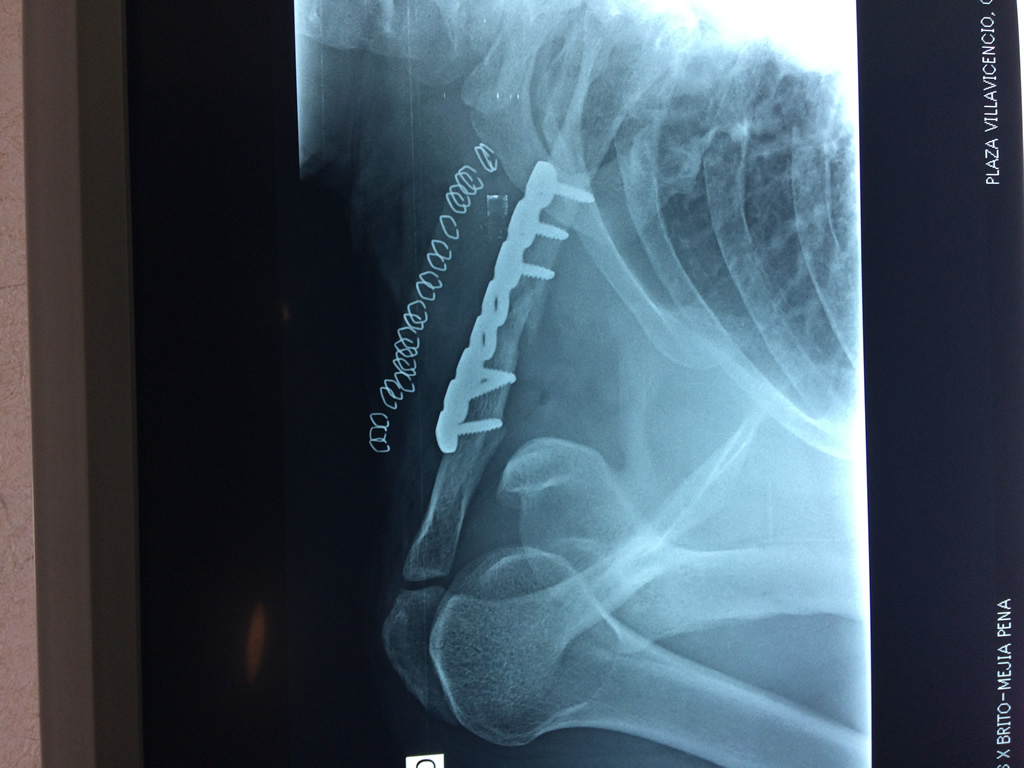

Fémur - Clavícula

La clavícula es un hueso largo, con forma de "S" itálica, situado en la parte anterosuperior del tórax. Junto con la escápula forman la cintura escapular. Se puede palpar por toda su longitud y se extiende del esternón al acromion de la escápula, siguiendo una dirección oblicua lateral y posterior.